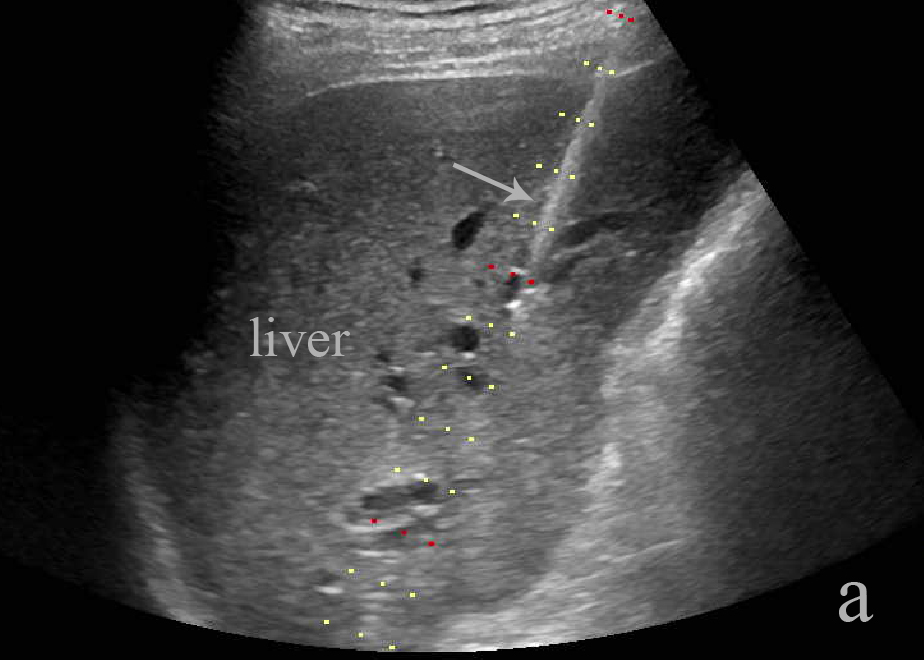

胆管穿刺置管-                                                                                                                         a超声引导胆管穿刺置管引流              b 超声引导胆囊穿刺置管引流                 c超声引导肾盂穿刺置管引流